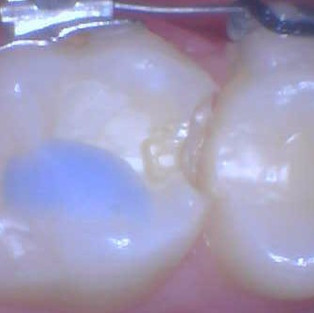

Chief Complaint: Patient presented with interproximal caries.

Not enough mechanical retention: The previous dentist performed a conservative slot preparation. Inadequate mechanical retention caused failure of the previous resin restoration.

Used #245 pear shaped to achieve buccal and lingual mechanical retention. Extended the pupal axial wall for bulk filled. Extended to the mesial pit for added resistance.

Used a small matrix band and cut into size. Wedged buccal and lingual for anatomy. Checked with mirror and removed all blood in the slot.

Used plow-sow technique to fill the box: Applied flowable composite, DO NOT CURE, applied packable composite. Used composite instrument to create anatomy. CURED. Air dried and applied another layer of flowable composite (like sealants)

Self-evaluation: Marginal ridge and contact were restored. Mesial pit was sealed.